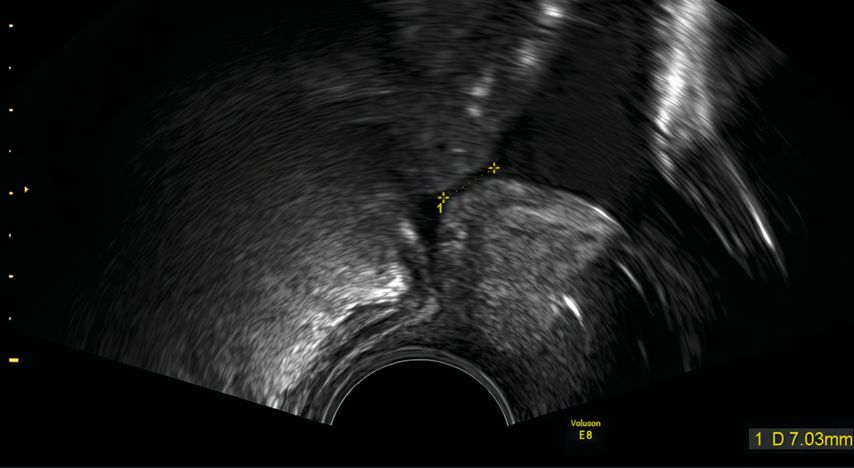

Im Folgenden werden jeweils für die drei wichtigsten asymptomatischen Risikokollektive (Schwangere mit kurzer Zervix (Abb. 1), Status nach Frühgeburt, Zwillingsschwangerschaften) die am häufigsten angewendeten präventiven Massnahmen vorgestellt. Zu den am meisten untersuchten Massnahmen gehören die

Kurze Zervix

Die Ergebnisse von Metaanalysen mit individuell erhobenen Patientendaten haben eine signifikante Reduktion der Frühgeburt von 18 auf 11% vor 33 (Schwangerschaftswochen, SSW) bei Schwangerschaften mit einer Zervixlänge unter 25mm (relatives Risiko, RR: 0,65; 95% CI: 0,45–0,94) und eine signifikante Verbesserung des neonatalen Outcomes (respiratorisches Distress-Syndrom, Gewicht unter 1500g, Verlegung auf die neonatologische Intensivstation) gezeigt.14